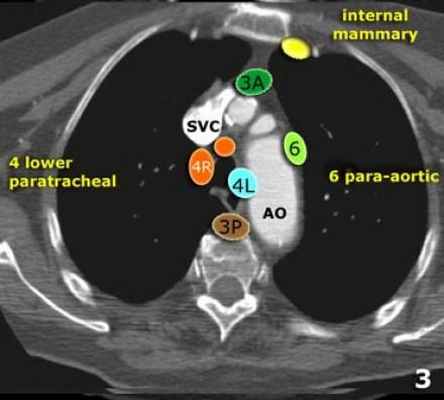

В этой статье представлены иллюстрации и КТ-изображения для лучшего понимания этой классификации.

3А Преваскулярные лимфатические узлы не примыкают к трахее как узлы 2 группы, а располагаются кпереди от сосудов (от задней стенки грудины, до передней стенки верхней полой вены справа и передней стенки левой сонной артерии слева)

3P Превертебральные(Ретротрахеальные) располагаются в заднем средостении, не примыкают к трахее как узлы 2 группы, а локализуются кзади от пищевода.

4R Нижние паратрахеальные от пересечения нижнего края плечеголовной вены с трахеей до нижней границы непарной вены, вдоль правой стенки трахеи до ее левой стенки.

4L Нижние паратрахеальные от верхнего края дуги аорты до верхнего края левой главной легочной артерии

6. Парааортальные лимфатические узлы лежат спереди и сбоку от восходящей части дуги аорты

На изображении слева 3А узел в преваскулярном пространстве. Обратите внимание так же на ниже расположенные паратрахеальные узлы справа относящиеся к 4R группе.

На изображении слева мы видим 4R паратрахеальные узлы. Кроме того здесь представлен узел кнаружи от дуги аорты, то есть 6 группы.

Группы лимфатических узлов на аксиальных компьютерных томограммах

3. Преваскулярные и ретротрахеальные: кпереди от сосудов (3А) и превертебральные (3Р)

4. Нижние паратрахеальные: ниже верхнего края дуги аорты до уровня главного бронха

6. Парааортальные: узлы лежащие кпереди и кнаружи от восходящего отдела аорты и дуги аорты под верхним краем дуги аорты.